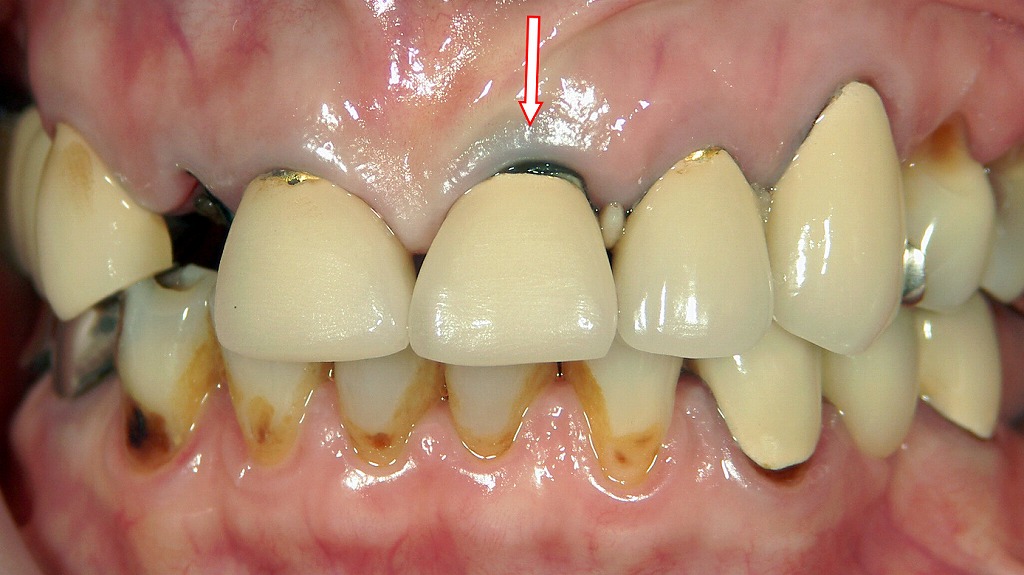

この画像は、上顎前歯部(特に左上1番)にメタルボンドクラウンが装着されている口腔内写真です。以下に詳細を説明します。

■ 左上1番の状態(矢印部)

赤い矢印で示された部分では、歯肉の縁に**灰青色の変色(メタルタトゥー)**が見られます。

これは、**メタルコアの素材が銀合金(シルバー合金)**であることが原因と考えられます。金属イオンが微量に溶出し、歯肉組織内に沈着することでこのような色調変化が起こります。

■ メタルボンドクラウンの特徴

左上1番のクラウンは、内面に金属フレーム(メタル)をもち、表層にセラミックを焼き付けたメタルボンド冠です。

経年的な歯肉退縮により、金属フレームの縁が歯肉付近で露出し、審美的な問題(黒っぽいライン)を引き起こしています。

🦷 臨床的考察

この症例は、銀合金メタルコアを使用したメタルボンドクラウンによる審美的問題の典型例です。

歯肉変色(メタルタトゥー)や歯周炎が進行しており、今後は**ファイバーコア+オールセラミック(またはジルコニア)**への再治療が望ましいと考えられます。